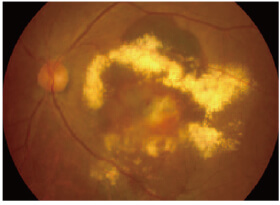

眼底検査

眼底に細い光を当て、網膜の状態を観察する検査です。

滲出型の場合は、出血や網膜のむくみなどが認められます。

滲出型加齢黄斑変性の眼底写真